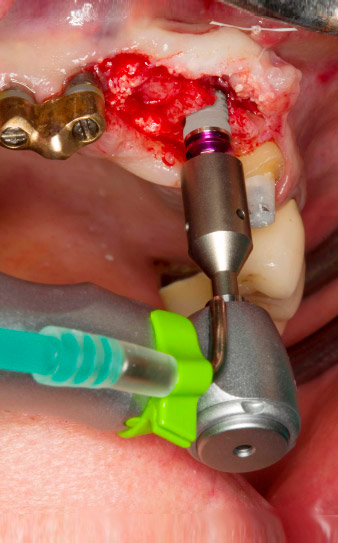

Der Alveolarknochen erweist sich an Position 22 als ausreichend dimensioniert. Die Abbildungen 2 und 4 zeigen die Implantatbett-Aufbereitung, den Gewindeschnitt und die Implantation mit dem Implantmed.

Der neue Implantologiemotor wird jeweils mit den geeigneten chirurgischen Winkelstücken von W&H verwendet.